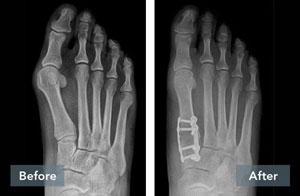

Lapiplasty® Before & After Results

The Positive Effect of Lapiplasty®

While traditional 2D osteotomy surgery merely cuts & shifts the bone to address the cosmetic bump, Lapiplasty® 3D Bunion Correction™ does more — it corrects the entire bone in 3D and secures the unstable foundation to get you back on your feet quickly in a walking boot. The Lapiplasty® Procedure has also shown low recurrence; 97% and 99% maintain 3D correction in 13 and 17 months respectively.